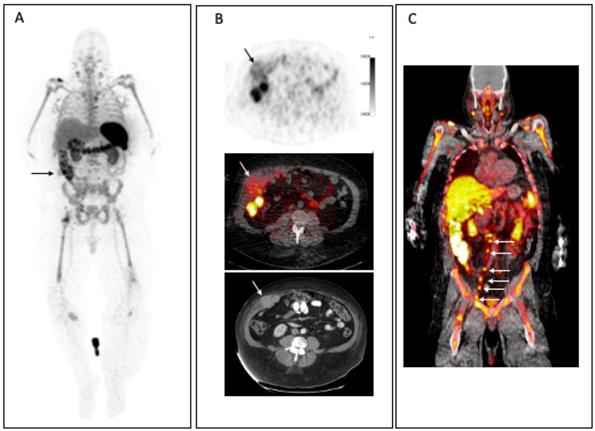

Figure 6

Radiolabeled 89Zr-atezolizumab imaging in patients showing heterogenous uptake within lesions in the thorax: (left) mediastinal lesion in a patient with lung cancer, (middle) abdominal wall metastatic bladder cancer, and (right) node in abdomen and metastatic bone lesion from breast cancer (arrows). (Adapted from Bensch E et al. Nat Med. 2018 Dec;24(12):1852-1858.)

Pembrolizumab and Nivolumab, FDA-approved monoclonal (IgG4) antibodies for targeting PD-1 receptors, have been radiolabeled with 64Cu or 89Zr for imaging (Table 2). Preclinical assessment with 89Zr-Pembrolizumab showed specific targeting of T cells in the spleen and in salivary and lacrimal glands, confirmed by tissue staining. The retained activity in tissue was long, with a liver clearance half-life of 168 hours [29]. Distribution of 89Zr-Nivolumab in healthy primates showed similar distribution with prominent uptake in liver, spleen, and lymph nodes, sites rich in T cell infiltration, confirmed with blocking of uptake with cold Nivolumab and histology analyses [30, 31]. Low uptake was noted in other tissues such as brain, heart, lung, kidney, and muscle, while the nodal uptake increased with time, suggesting continuous binding to T cell and accumulation. Atezolizumab and Durvalumab antibodies target PD-L1 and are FDA-approved for the treatment of certain malignancies, either as a single agent or in combination with other agents. Imaging with 89Zr-atezolizumab in 22 patients with either NSCLC, triple-negative breast cancer, or bladder cancer showed good targeting of tissues and lesions with PD-L1 expression, as correlated with immunohistochemistry [32]. There was prominent splenic, nodal, and bone marrow uptake and correlation of uptake to CD8 expression was noted in spleen though some uptake was also noted in some sites of inflammation. Tumor uptake was heterogenous and varied between tumor types and sites of lesions (Figure 6). Lower uptake was noted in breast cancer lesions compared to bladder or lung cancer and in bone lesions compared to liver lesions. Higher 89Zr-atezolizumab uptake in lesions was noted in those with better response and 89Zr-atezolizumab uptake showed better correlation than with immunohistochemistry or RNA-sequencing-based predictive biomarkers [32]. 89Zr-atezolizumab imaging may be useful to stratify and identify patients with RCC who are most likely to benefit from PD-1/PD-L1-directed treatment [33]. 89Zr-Durvalumab imaging trials in head and neck cancer and NSCLC undergoing treatment with durvalumab are underway [34] (NCT03853187 and NCT03829007).